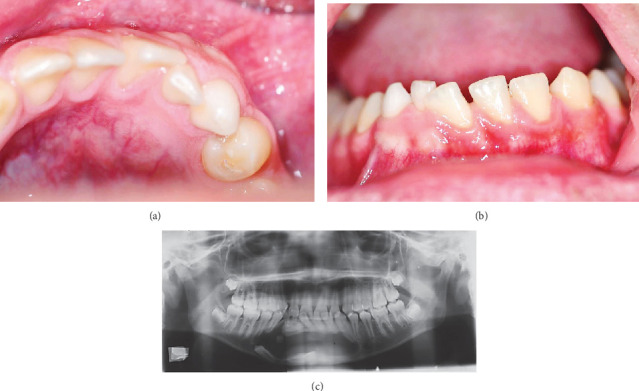

A calcifying odontogenic cyst (COC) is a cystic lesion originating from odontogenic epithelium, exhibiting ameloblastomatous features and containing focal accumulations of ghost cells. The standard treatment for COC typically involves enucleation followed by surgical curettage. However, if the cyst is large or closely associated with anatomical structures, decompression may be considered as a preliminary step before enucleation. A 12-year-old male patient presented with swelling in the anterior mandibular region. Radiological assessment revealed an extensive radiolucent area crossing the mandibular midline, accompanied by radiopaque areas within the lesion. The diagnosis of COC associated with compound odontoma was confirmed. The treatment plan involved decompression, followed by enucleation. After over 9 years of follow-up, the patient showed satisfactory and effective outcomes, with no signs of recurrence. This therapeutic approach minimizes the morbidity and cost associated with extensive and invasive reconstructive surgeries.